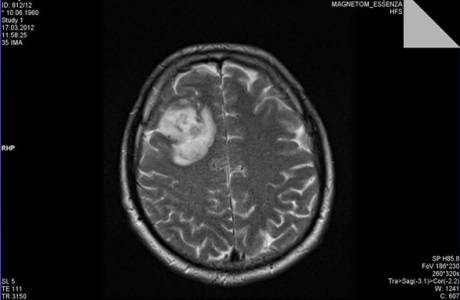

- Diferentes tipos de estudos de raios-x (tomografia computadorizada, ressonância magnética, pneumografia, angiografia). Então, determine a localização exata, direção de crescimento do neoplasma, composição histológica.